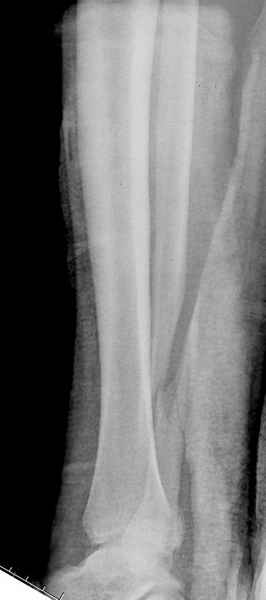

>На сделанных у нас снимках видно, что не все благополучно...

Неравномерность суставной щели может быть связана с разрывом глубокой порции дельтовидной связки и ротацией м/берцовой кости за счет поврежденных структур синдесмоза(репозиция ее на уровне перелома как-будто удовлетворительная).

По моему мнению,ассиметрия суставной щели обусловлена импрессией медиальной части суставной поверхности б/б кости. Да, позиционный винт здесь не лишен, но через 4 недели целесообразность его проведения сомнительна, брейс, ограничение осевой нагрузки достаточно.Есть еще деонтологические аспекты повторной операции, не все так плохо выполнено предыдущим доктором!

Импрессия медиальной части суставной поверхности бывает при супинационном механизме перелома лодыжек (тип А по классификации АО). Здесь механизм пронациия+наружная ротация (тип С, синдесмоз и межкостная мебрана повреждены),

перелом медиальной лодыжки отрывной, при этом в 20-30% бывает повреждение дельтовидной связки.

Клиновидность щели сустава следствие повреждения дельты, невосстановления длины малоберцовой или (хотел сказать "установки в гипсе", но оного, вроде,

нет)? Устранить бы причину. А равно как и тенденцию" к наружному подвывиху. Чрескостный остеосинтез - метод выбора.

Мое мнение, что никакой ротации малоберцовой кости здесь нет и синдесмоз тоже впорядке. Все дело в некачественно репозиции медиального мыщелка. Скорее всего его или немного ротировали при операции или сместили латерально. Более склонен ко второму варианту.

Расширенная медиальная щель более чем на 4 мм и укорочение малоберцовой более чем 2 мм, а перелом заднего края большеберцовой смещения более 2мм с вовлечением 30% поверхности сустава, считается отходом от нормы голеностопного сустава, и подлежит к оперативному вмещательству.